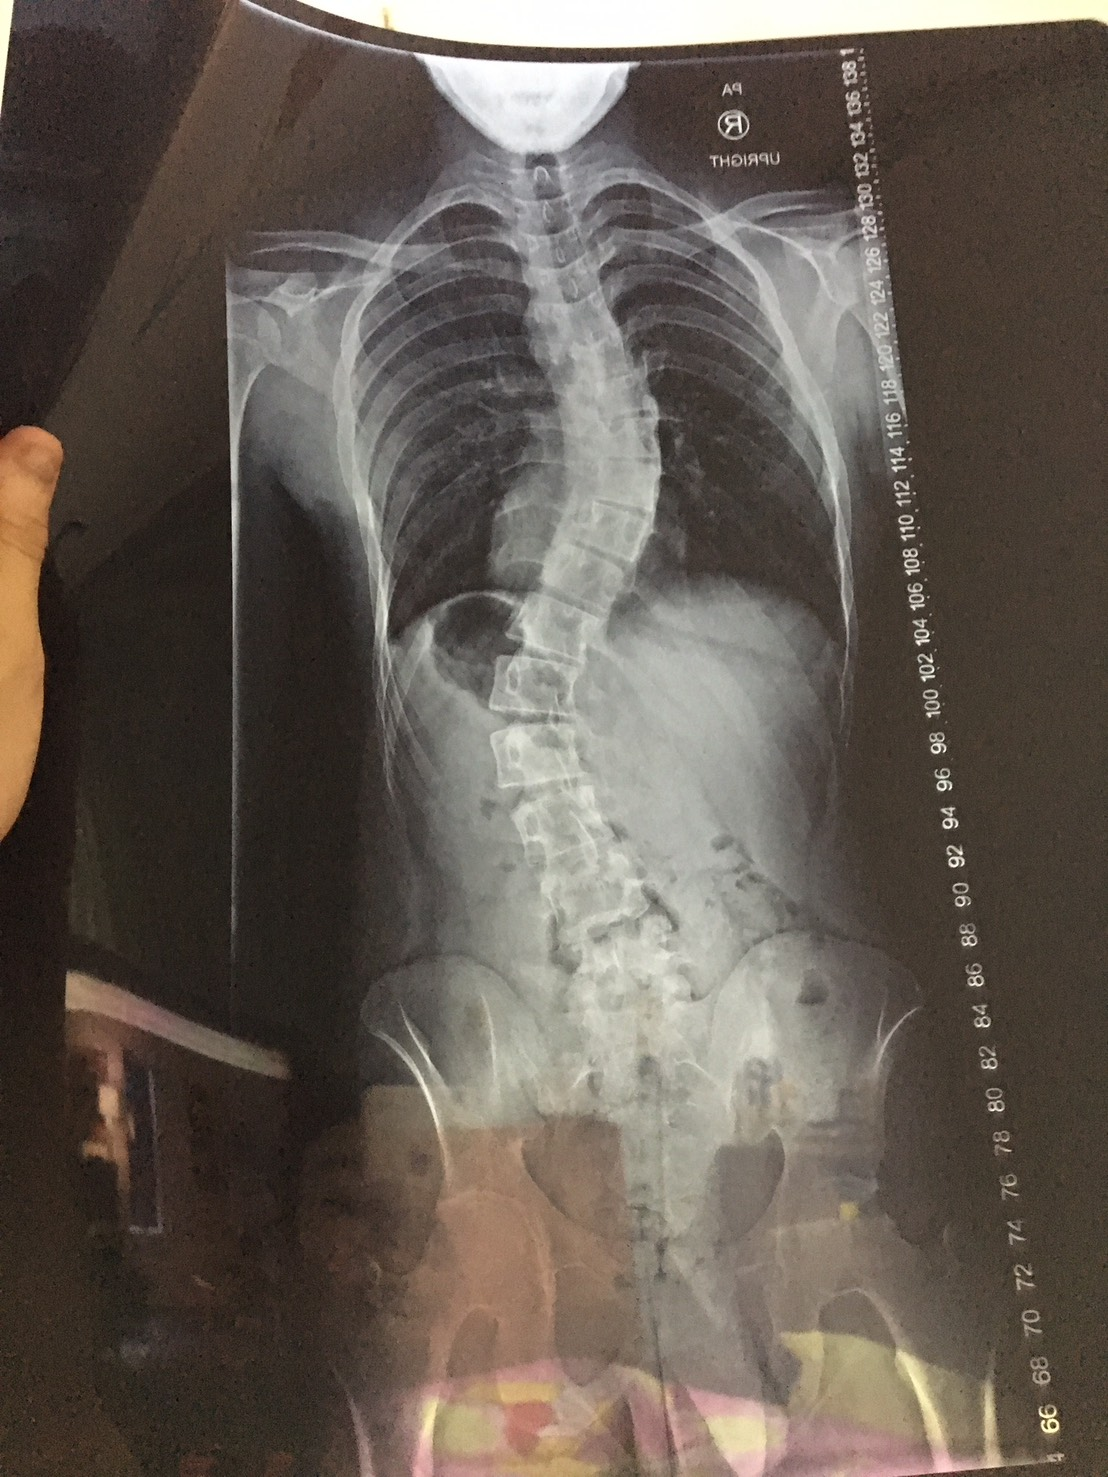

킴이랑 자연스럽게 토크를 하게 되었는데 킴은 지금 교수님이랑 사이가 썩 좋은 편은 아니고... 같이 프로젝트하는 교수님들이랑 오히려 사이가 더 좋다... 지금 심포지엄 준비중이고 이거 끝나면 박사 연구는 거의 놓을 거고 졸업하면 킨다이에 젠더 이슈를 위한 NLP라는 주제로 연구하러 포닥으로 갈 거다.. 요새 갑상선에 문제 있고 멘탈도 안 좋아서 힘들다... 졸업하고 포닥 가기 전에 척추측만증 수술 받으면 키가 7~9cm 커질거라길래 뭔소리냐고 했는데...